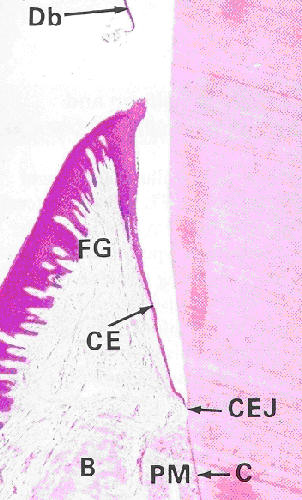

| Fig. 13.9 |

Young and Heath p. 243 |